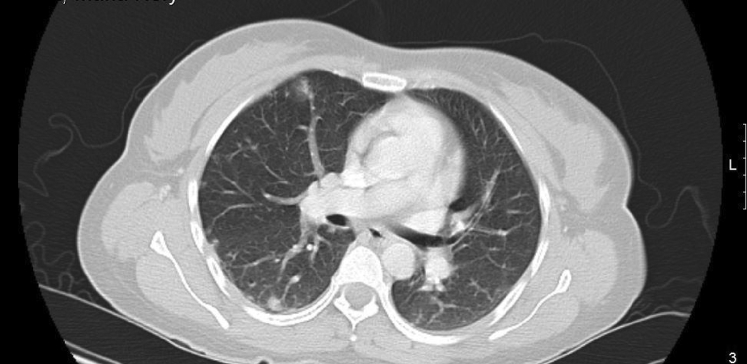

The patient continued to experience vaginal bleeding and her repeat hemoglobin level was 4.8 g/dL. She received 2 units of packed red blood cells. Because of her elevated beta-hCG without evidence of intrauterine pregnancy on ultrasound, additional testing was ordered for possible metastasis of GTN. CT imaging of her chest revealed small nodules, some with ground glass halos, scattered throughout both lungs (Figs. 1 and 2). These findings were interpreted by radiology as consistent with metastatic lung disease from choriocarcinoma.

Fig. 2.

Middle lung.